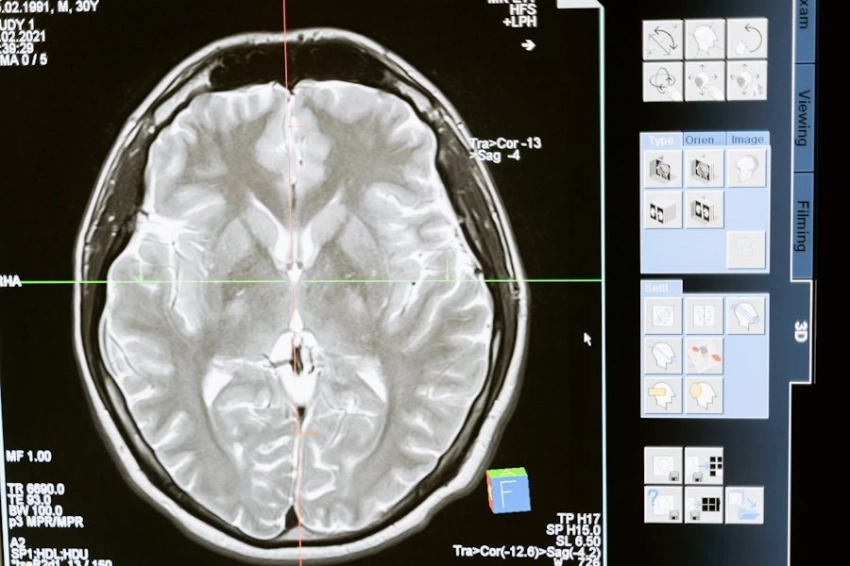

Болезнь, ставшая известной благодаря психиатру Алоису Альцгеймеру, носит его имя и представляет собой поражение мозга, при котором пациент утрачивает способность к нормальному воспоминанию. Еще совсем недавно это заболевание было характерным для пожилых людей, старше 65 лет, но последние исследования показывают, что болезнь значительно «помолодела». Уже люди сорока лет находятся в зоне риска.

Кроме того, крайне важно пройти раннюю диагностику, поскольку на ранних стадиях болезнь Альцгеймера поддается более эффективному лечению, что помогает значительно замедлить её прогрессирование.